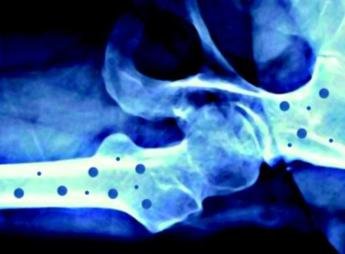

(Adnkronos) – In occasione della Giornata mondiale dell’osteoporosi, che si celebra il 20 ottobre sul tema ‘Dite no alle ossa fragili', Feidos, Federazione italiana osteoporosi e malattie dello scheletro, rinnova il suo impegno per la salute delle ossa con nuove iniziative a supporto dei pazienti. L’osteoporosi – ricorda una nota – è una patologia che colpisce almeno 5 milioni di persone in Italia e 200 milioni nel mondo, e la cui incidenza è destinata a crescere nel prossimo futuro. Su questa malattia ormai globale, Feidos accende i riflettori sensibilizzando la popolazione sull’importanza di adottare sani stili di vita per migliorare lo stato di salute delle ossa, in particolare attraverso una corretta alimentazione, un’adeguata e regolare attività fisica, nonché prestando attenzione ai fattori di rischio individuali. Nelle giornate del 20 ottobre, ad esempio, si potrà richiedere un consulto telefonico gratuito con un medico specialista chiamando il Numero Verde 800 909225 e, recandosi presso uno degli ambulatori aderenti all’iniziativa elencati sul sito fedios.org, si potrà accedere a un controllo gratuito del rischio di osteoporosi. L’impegno di Feidos è quello di garantire ai pazienti un supporto continuo attraverso campagne d’informazione, impiego di volontari presso le strutture ospedaliere, indagini con l’obiettivo di individuare bisogni, criticità ed eventuali buone pratiche per facilitare l'accesso alle terapie più appropriate. Anche quest’anno la Federazione consolida la partnership con l’associazione pazienti Mamog, Mamme con osteoporosi gravidica. L’obiettivo comune è di fornire informazioni circa questa patologia che causa fratture spontanee durante l’ultimo trimestre di gravidanza e nel puerperio. Sempre a sostegno dei soggetti affetti da osteoporosi, Feidos inaugura anche il legame con un nuovo partner, il gruppo Ffn, Fragility fracture network Italia, la parte italiana di un’organizzazione internazionale, la Ffn che ha come obiettivo quello di creare una rete multidisciplinare di esperti per ottimizzare la gestione e la prevenzione secondaria delle fratture da fragilità.

L’iniziativa ha il supporto incondizionato di Ibsa Farmaceutici Italia come main sponsor, e di Gedeon Richter, Organon, Accord Healthcare Italia, Ucb e Theramex come silver sponsor. Sono le aziende farmaceutiche che hanno scelto di sostenerne questi importanti progetti di informazione che, grazie a loro, possono essere portati avanti. L’osteoporosi – conclude la nota – è una malattia sistemica dell'apparato scheletrico, caratterizzata da una bassa densità minerale e dal deterioramento della micro-architettura del tessuto osseo, con conseguente aumento della fragilità ossea e del rischio di fratturarsi. —salutewebinfo@adnkronos.com (Web Info)